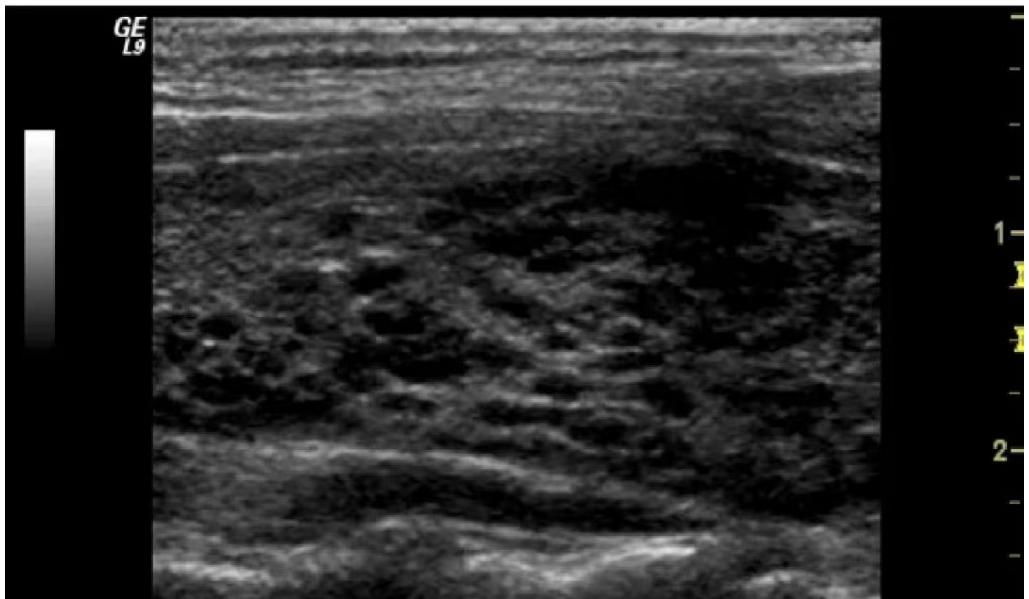

桥本氏甲状腺炎的超声表现,及妊娠注意事项

桥本氏甲状腺炎是一种常见的自身免疫性疾病 ,尤其多发于女性。 超声检查在该病的诊断中扮演着重要角色 。典型的超声表现包括甲状腺正常或增大,实质回声弥漫性减低,内部有网格状、条索状强回声。这种特征性的影像学改变有助于医生及时发现疾病,为早期诊断提供依据。